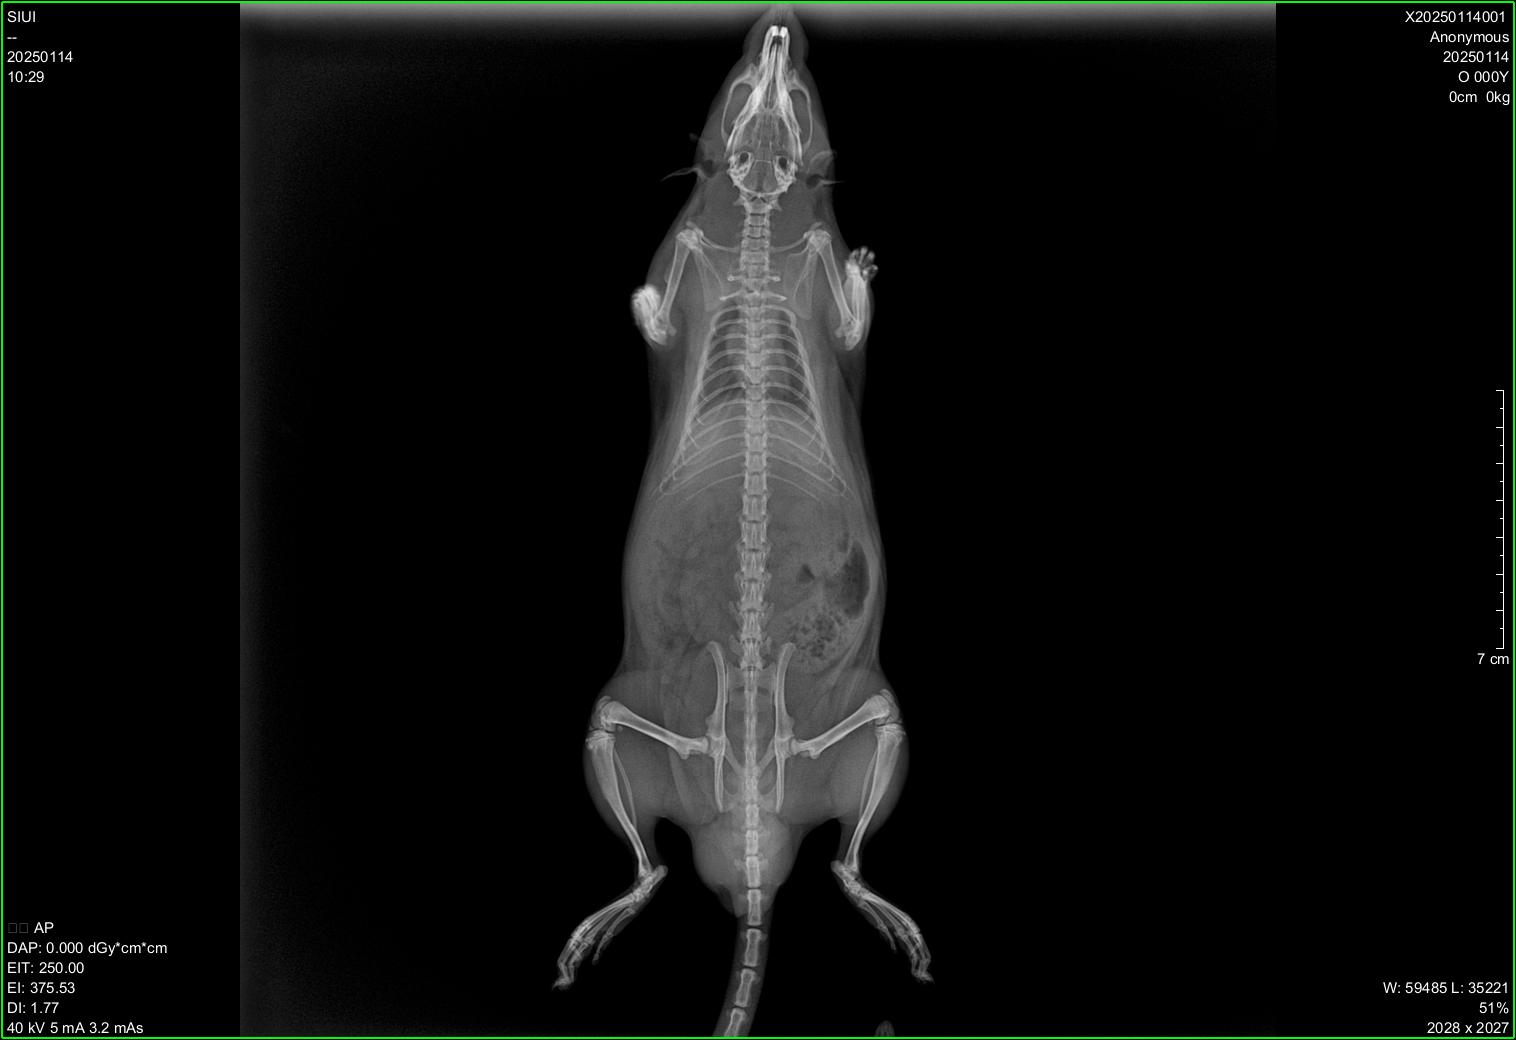

Veterinary Ultra-Portable DR System

SIUI veterinary ultra-portable DR system currently includes 2 models, SR-100 Vet and SR-300 Vet. An ultra-portable DR system consists of an ultra-lightweight X-ray generator, a wireless flat panel detector, and a user-friendly workstation.

The X-ray generators of SR-100 Vet and SR-300 Vet feature different portable designs, thereby accommodating the operational preferences of different veterinarians and adapting to diverse application environments. All-in-one backpacks, suitcases, and various types of stands are available for convenient transportation and application at stables, farms, zoos, etc.

Diverse Application Scenarios:

● Animal research institutions